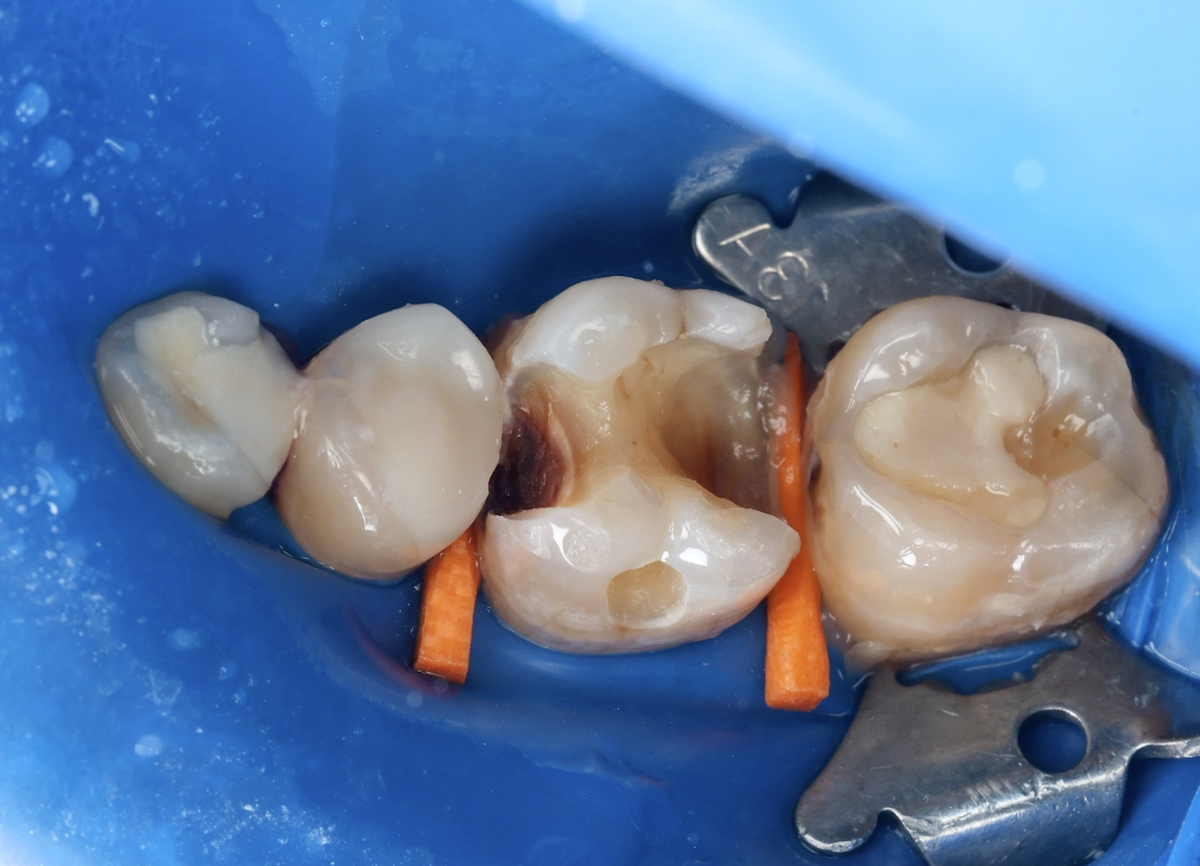

CID и CAD дентин - какой кариес убираем, а какой можно оставить

"Доктор, а почему Вы кариес оставили?" - недоумевает пациент, рассматривая с терапевтом фотографии этапов лечения его зуба. А вы знали, что не весь тёмный кариес нужно убирать всегда в ноль при лечении? Что поражённый кариозным процессом дентин бывает разным и, в звисимости от его вида, врач выбирает ту или иную тактику и от этого зависит даже сохранение жизнеспособности пульпы. Ну, или несохранение. Мы с Елизаветой Дмитриевной Тирик, врачом-стоматологом клиники Parodent, решили поднять тему, которая будоражит умы любопытных и глазастых пациентов, а остальные об этом никогда в жизни не догадались бы. Зачем оно вам надобно? Да интересно же. Ну и полезно. Рассматривая с врачом сделанные во время приёма фотографии лечебного процесса, можно понять, что вон то подозрительное пятно - вовсе не опасность, а CID дентин. От того, как врач работает с кариозным дентином, зависит: Слишком мало кариозных тканей убрали - оставили инфекцию, кариес продолжит разрушать зуб под пломбой. Слишком много

Когда кариес пробирается через эмаль и достигает дентина, он не поражает его равномерно и одинаково. Формируются разные слои с разной степенью разрушения.

CID (сaries-Infected dentin) - дентин, инфицированный кариесом. Это слой, где инфекционный процесс уже идёт полным ходом. Ткань разрушена, бактерии проникли глубоко, коллагеновые волокна денатурированы. Этот дентин мягкий, рыхлый, при препарировании, буквально, разлетается хлопьями в разные стороны.

CAD (caries-affected dentin) - дентин, хоть и поражённый кариесом, но ещё не достигший стадии необратимого разрушения. Структура изменена, но коллагеновый каркас сохранён и инфекционная нагрузка минимальна. Ткань способна к реминерализации.

То есть, первым слоем идёт CID, потом CAD.

Представьте глубокую кариозную полость. Врач начинает препарирование.

Верхние слои - CID дентин. Мягкий, хлопьями разлетается в разные стороны при работе бором. Экскаватор (ручной инструмент) проваливается, как в масло. Этот слой убирается полностью.

Глубже - CAD дентин. Плотнее, но ещё не такой твёрдый, как здоровый. Под ним - пульпа. До неё может быть меньше миллиметра.